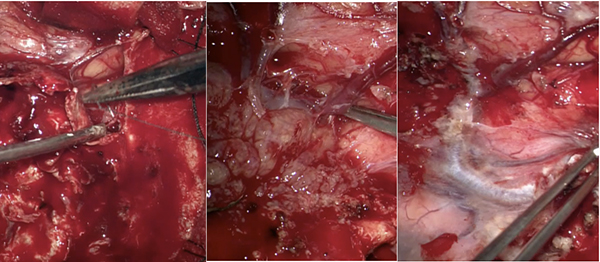

手术过程

Step1、切开皮肤,分离侵袭到皮下的肿瘤,铣刀去除骨瓣,切除皮下病损+被侵袭的颅骨

手术细节:骨瓣可分块取除,避免肿瘤粘连引起脑组织、静脉及矢状窦的损伤

Step2、切除大脑镰前部肿瘤、切除大脑镰

手术细节:肿瘤底部大脑前动脉及分支供血,需要小心分离保护血管

Step3、切除功能皮层肿瘤、尽可能切除侵袭到静脉窦的肿瘤+矢状窦修补,小心分离中央沟静脉,避免损伤任何皮层静脉。

手术细节:尽量切除贴附静脉窦肿瘤、分离中央沟静脉级分支,务必保护皮层引流静脉

Step4:进行硬膜修补,个体化补片修补缺损颅骨

手术细节:人工硬膜修补+补片修补